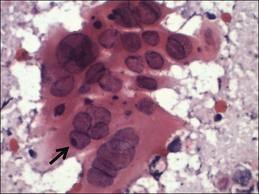

Dx?

Chlamydia trachomatis

(Cytoplasmic inclusion bodies [vacuoles containing bugs] = Ct)